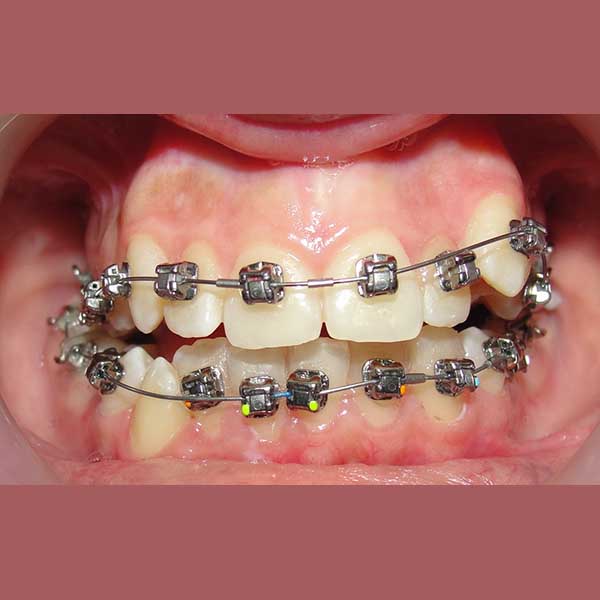

كما تظهر الصور، نجحنا في رصف الأسنان بشكل ممتاز وتحقيق إطباق مثالي. عاد الناب المرتفع إلى مكانه الطبيعي ضمن ابتسامة متناسقة وجميلة، مما أعاد لمراجعتنا الثقة والسعادة بابتسامتها.